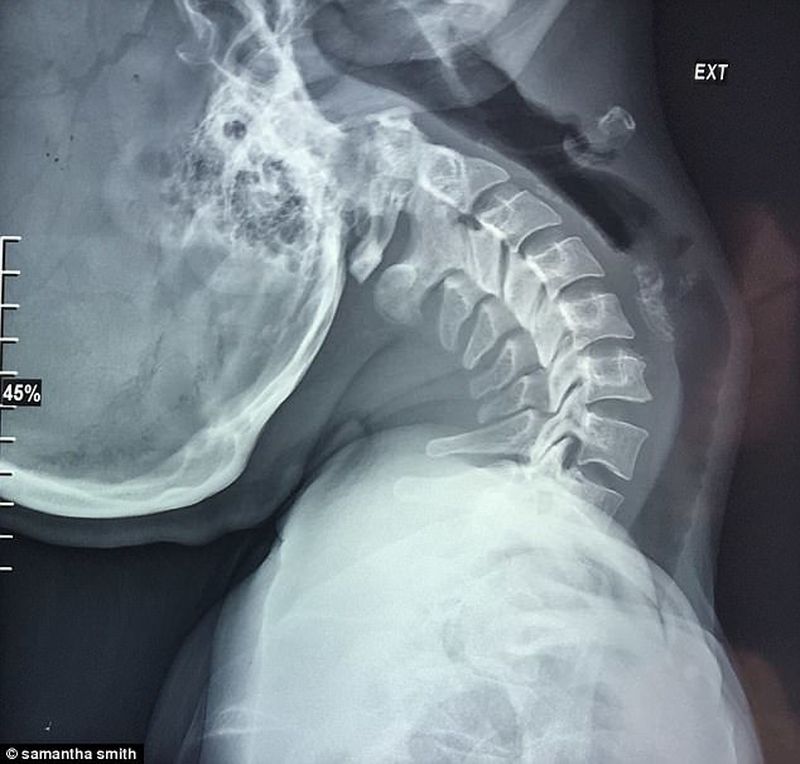

Samantha Smith, o femeie de 30 de ani din Marea Britanie, sufera de o boala rara si periculoasa. Musculatura gatului nu ii poate sustine grautatea craniului, astfel ca, in timp, coloana sa vertebrala din zona cervicala sa-i fie strivita in momentul in care sta in pozitie verticala.

Samantha sufera de aceasta afectiune de 30 de ani şi a ajuns intr-un stadiu atat de avansat, incat doctorii i-au mai dat de trait doar o luna, fiind apoi „decapitata” de propriul craniu pentru ca nu poate fi sustinut pe vertebre, noteaza Daily Mail.   Exista doar trei chirurgi in lume care fac operatia de care Samantha are nevoie, doi in SUA si unul in Barcelona.